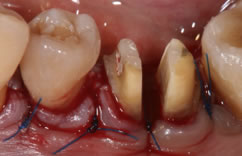

歯周病が進行すると、治療器具が届かないほど歯周ポケットが深くなることがあります。こうなると、通常の方法では歯周ポケットの中の歯石を取り除くことはできません。

このような場合は、外科的に歯肉を切り開いて歯石などを取り除く「歯周外科治療」を行います。

「FOP法」は、歯肉を切り開いて奥深くの歯石を取り除く術式です。直接目で見ながら歯石を取り除けるので、ほとんど取り残しがありません。